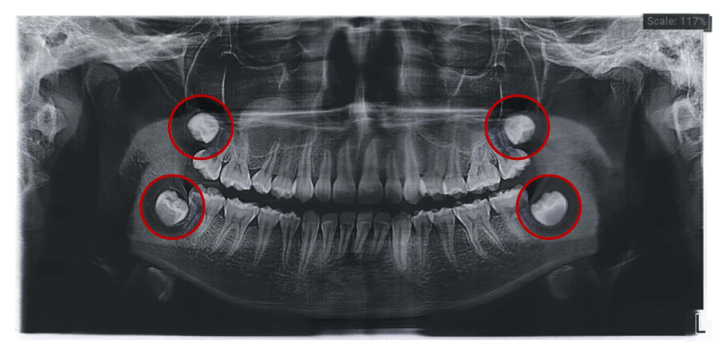

親知らずとは、正式には第三大臼歯(だいさんだいきゅうし)と呼ばれる、人間の永久歯のなかで最も遅く生える奥歯のことを指します。10代後半から20代前半にかけて上下左右の奥歯の一番後ろに1本ずつ生えるのが一般的ですが、なかには1本も生えてこない人もいます。3本しか生えない人や、2本しか生えていない人もいます。

生える本数や生え方に個人差があるのが特徴で、斜めや横向きに生える、歯ぐきの中に埋まったままになるといった方も珍しくなく、トラブルの原因になることもあります。

スムーズに抜ける場合は費用を抑えられますが、歯茎に埋まっていたり、生える角度の問題で抜歯の難易度が上がる場合には、追加の処置が必要となり費用が高くなることも考えられます。CT撮影などが必要なケースでは、追加で1,000円〜2,000円程度かかることもあるでしょう。